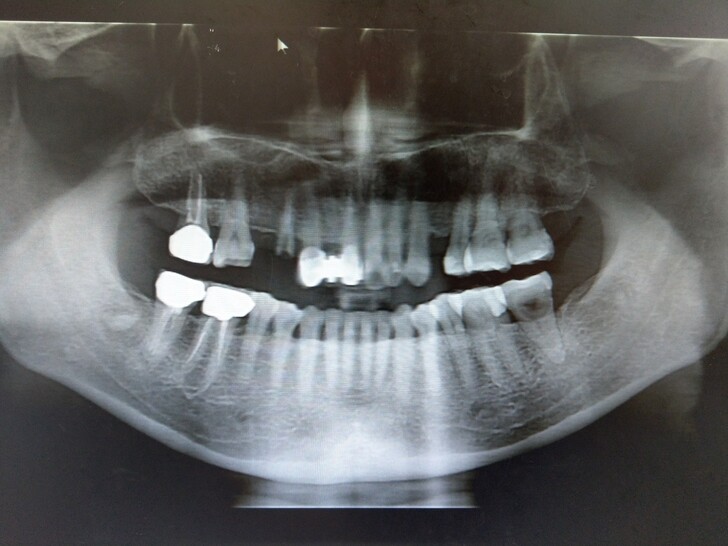

透過新華院內那台3D斷層掃描機器把上下顎骨頭密度細節掃得一清二楚

牙齒骨健康就能省下植牙骨質不足的費用不用補骨粉囉

這時不得不稱讚設備先進還是有許多優勢地

一般舊型牙科通常都只有X光機植牙費用雖然報價誘人

但在清水牙科診所說要植牙前還要先跑一趟放射所自費三千拍攝3D植牙用口腔X光片

取片後牙醫師才能評估怎麼做植牙

透過3D數位資料林醫師還特別說明哪個部分牙齒骨頭密度好

只要有做過根管治療上過牙釘位置骨質密度就會受到影響